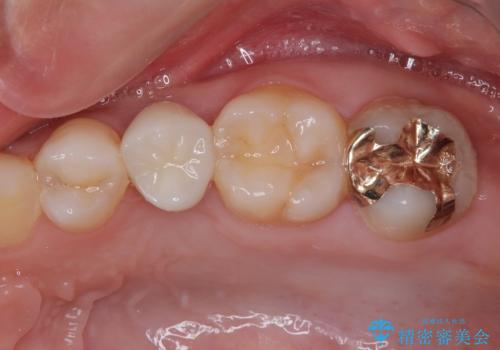

- 左上の前から5番目の金属の詰め物(メタルインレー)が取れたとのことで来院された患者様です。一時帰国中とのことで短期間での治療を希望されていました。土台はファイバーコアがしっかり入っていたため、そのまま利用することにしました。根管治療は症状もなく、レントゲン上でも病変を認めないため患者様と相談して根管治療を行わないことにしました。拡大鏡の視野下において、虫歯を除去して元々の詰め物の範囲も大きいためオールセラミッククラウンに適した形に整えました。